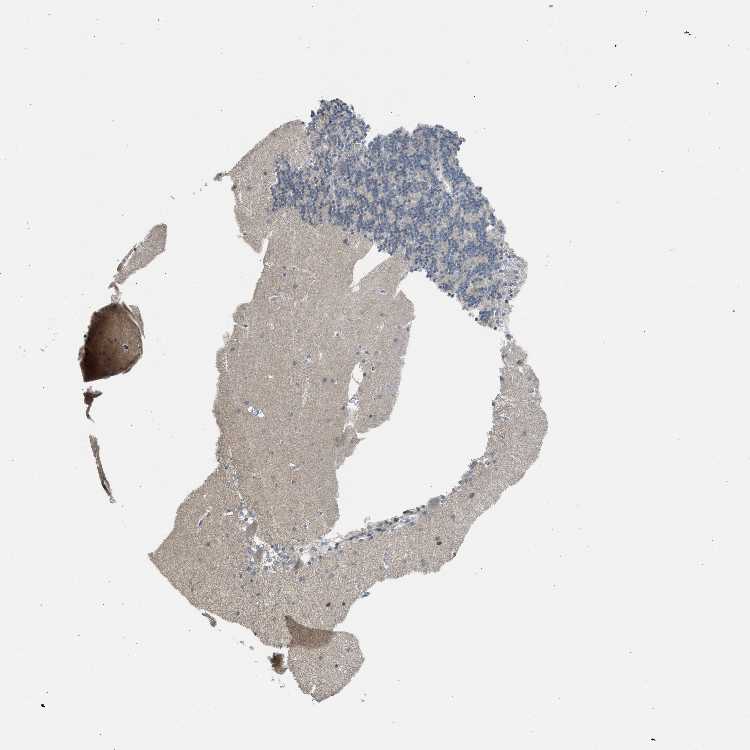

CEREBELLUM - Antibody stainingi

Antibody staining in the annotated cell types in the current human tissue is reported as not detected, low, medium, or high, based on conventional immunohistochemistry profiling in selected tissues. This score is based on the combination of the staining intensity and fraction of stained cells.

Each image is clickable and will lead to virtual microscopy that enables deeper exploration of all samples and also displays staining intensity scores, fraction scores and subcellular localization as well as patient and tissue information for each sample.

Antibody HPA018113

Purkinje cells Low

Cells in granular layer Not detected

Cells in molecular layer Not detected